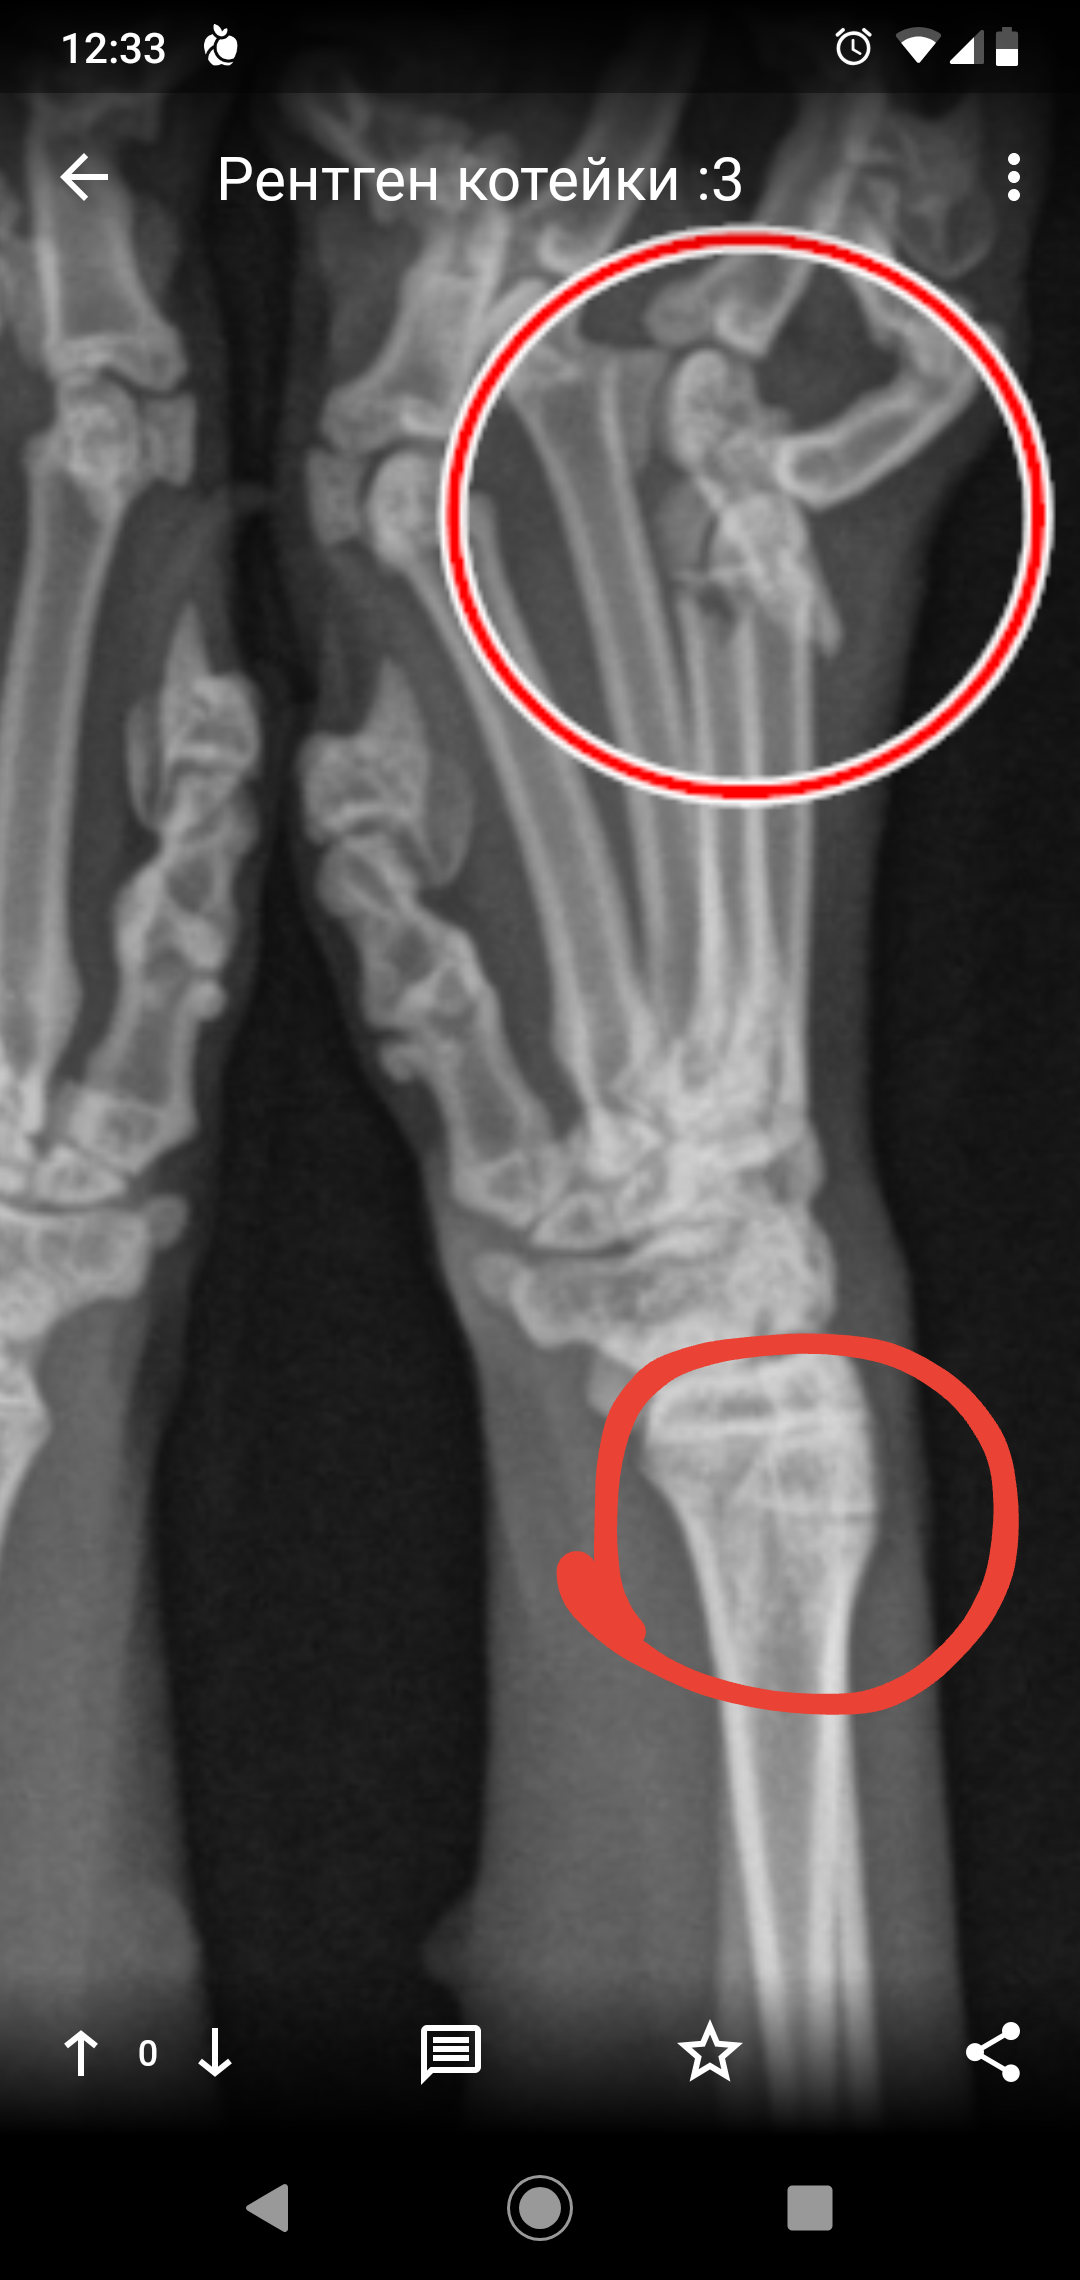

Вот как-то так выглядит кот напросвет. Теплоты там особо не видно, зато есть целый комплект косточек и перелом четвертой пястной кости.

Пока люди отвернулись, Линукс порвал сетку, вышел погулять на карниз и превратился в ракету класса "окно-асфальт".  Жив, цел, орёл, месяц ходил со спицей в лапе, и всё равно умудрялся буянить по ночам.

Перелом четвертой пястной кости.